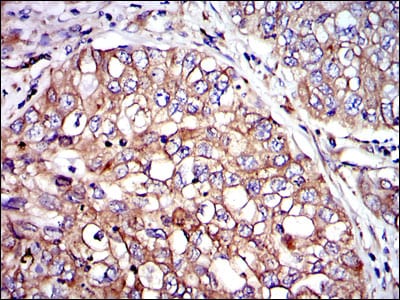

Immunohistochemical analysis of paraffin-embedded human intima cancer tissues using CRK mouse mAb with DAB staining.

Immunohistochemical analysis of paraffin-embedded human lung cancer tissues using CRK mouse mAb with DAB staining.